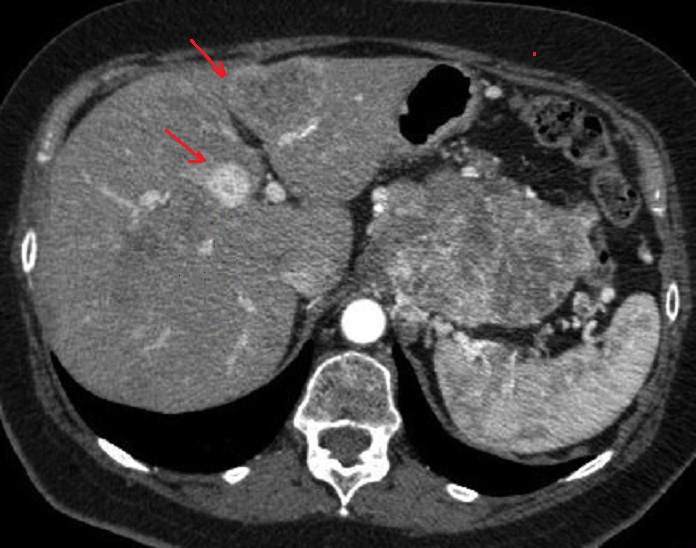

90% des tumeurs endocrines

non fontionelles avaient de lesions metastasiques

locaux ou a distance . Image radiologique TDM du

metastase hepatique foie droit d'un tumeur

pancreatique non fontionelle ( fleche rouge ) |